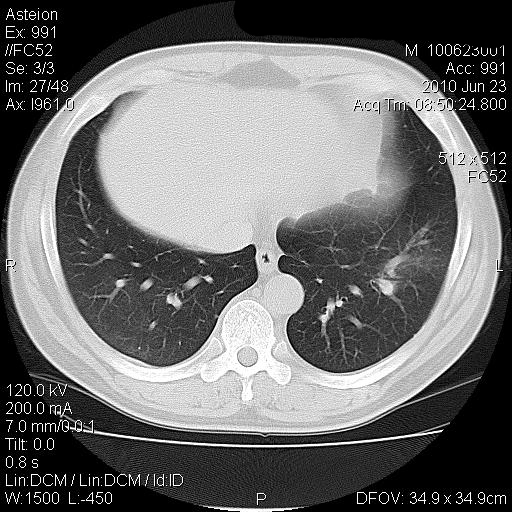

男 41岁 因发烧38-39度 这几天消炎治疗

化验结果 中性粒细胞比率升高(80.9) 淋巴细胞比率下降(10.2) 红细胞压积下降(33.4)

血小板平均分布密度升高(18.9)

双肺炎性灶【密度高 局限 考虑金葡菌 产血浆凝固酶所致】

病灶位于两上肺及右肺下叶背段,建议抗炎治疗后复查;结核不排外。

双肺炎性渗出病变,以右下肺为著。考虑金葡菌感染。

两肺多发结节斑块影,右下见支气管气相,支持两肺多灶性感染,抗炎治疗后复查。

双肺多发大小不等的团片状病灶,周围较模糊可见晕征,未见明显分叶征,纵膈淋巴结未见肿大。

考虑炎性病变。

双肺多发大小不等的团片状病灶可见于肺部炎性肉芽肿,也可见于肺淋巴瘤、肺淋巴瘤样肉芽肿、肺结核、肺部肿瘤,本例的影像表现结合临床考虑肺部炎性病灶。